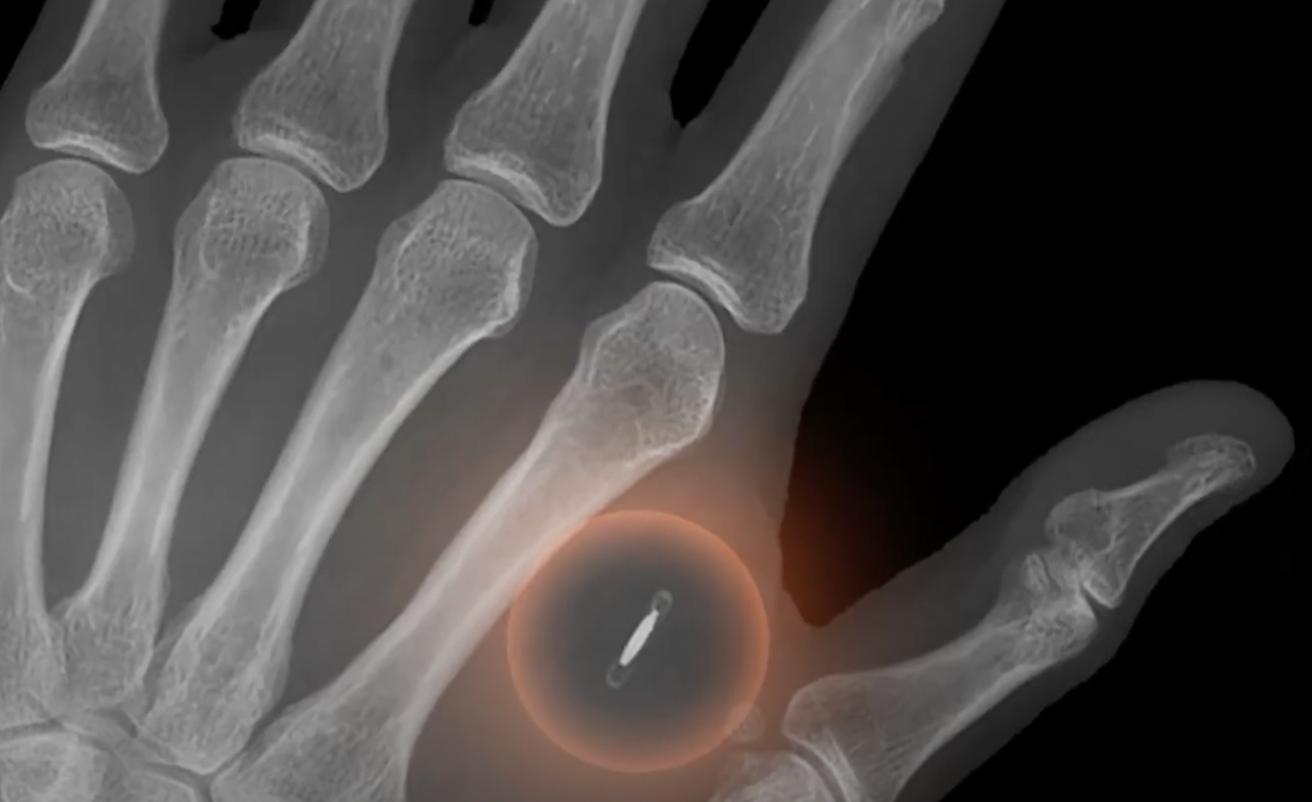

Profesional IT yang menyebut dirinya sendiri dengan nama F418 ini mengatakan, percobaan tersebut dilakukan agar transaksi pembayaran dengan Bitcoin bisa dilakukan dengan mudah, langsung menggunakan tangan, tanpa perlu kartu atau smartphone.

Meski tampak mudah, F418 mengungkapkan ada risiko medis di balik penggunaan chip ini. Jika proses penanaman chip gagal dan harus diulang, ada risiko infeksi yang besar.

Percobaan tanam chip Bitcoin pertamanya juga sempat gagal dan ia harus meminta bantuan medis profesional untuk melakukan operasi pengeluaran chip dari tangannya.

Namun, percobaan kedua berhasil. Chip yang ditanam di tangan kanannya bisa digunakan untuk melakukan pembayaran dengan Bitcoin melalui layanan Lightning Network, tanpa rasa sakit.

Chip yang ditanam dilengkapi dengan teknologi Near Field Communication (NFC), yang penggunaannya sudah semakin populer di dunia Bitcoin. Teknologi NFC di Lightning Network mulai banyak dipakai setelah kemunculan Bolt Card yang resmi tersedia di Isle of Man dan El Salvador.